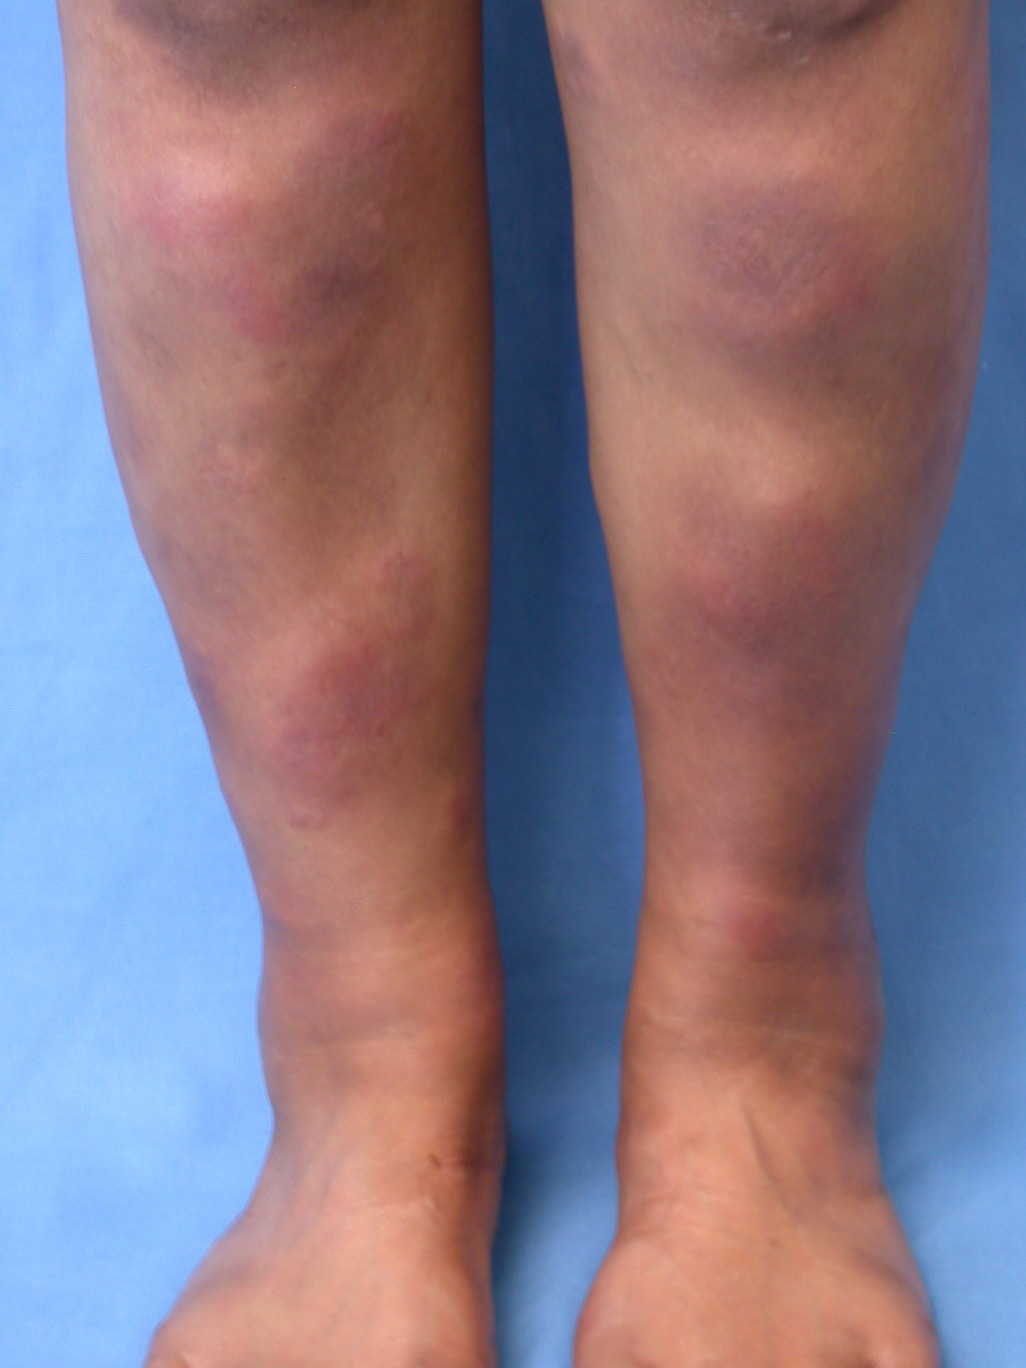

Erythema nodosum ses bl.a. ved infektioner, sarcoidose og inflammatoriske tarmsygdomme.

Erythema nodosum

- Er en inflammation i det subkutane fedtvæv, på dansk kaldet knuderosen

- Traditionelt associeret med tuberkulose, men i dag hyppigere associeret med streptokokinfektion i svælget. Kan også skyldes andre infektioner eller være udløst af medikamenter. Relateret til inflammatoriske tarmsygdomme. Sarcoidose må udelukkes, da det er en hyppig årsag til erythema nodosum hos unge kvinder